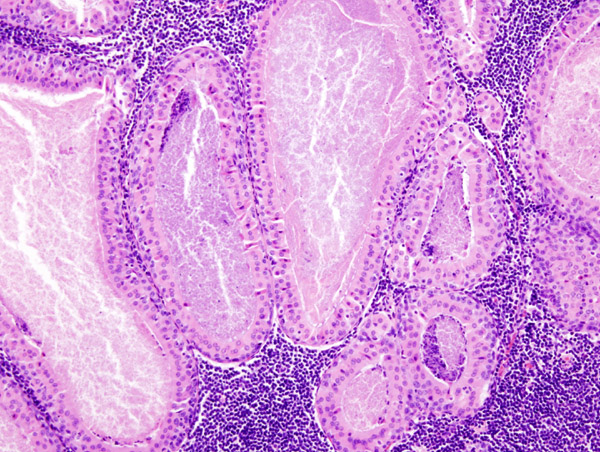

Warthin Tumor

Warthin tumor is a benign cystic tumor with a stroma that resembles a lymph node and many lymphocytes.

Warthin tumor is also known as papillary cystadenoma lymphomatosum.

Warthin tumor is the second most common salivary gland tumor.

Warthin tumor occurs almost invariably in the parotid.